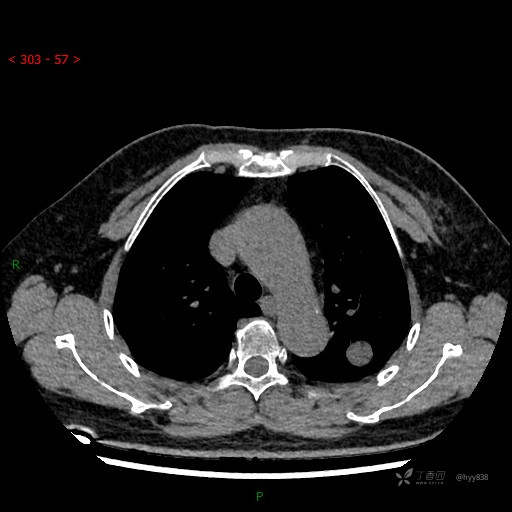

静脉期

各期CT值:28hu、58hu、69hu